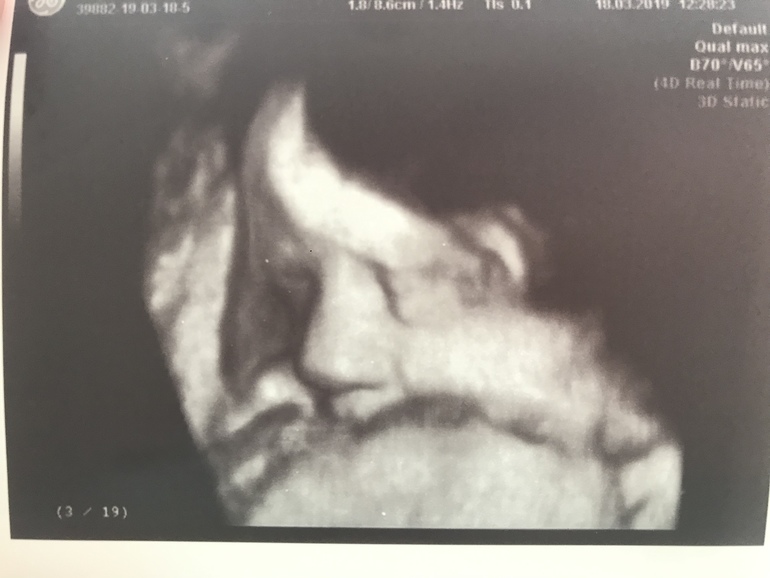

Вес 1901гр😍

Он много раз сказал, что это папина дочка (ресницы длинные, губы пухлые, головка большая)❤️ А волосы в маму «будет светлая шатенка, волосы кудрявенькие»😁

Всё УЗИ была серьёзная, а тут улыбнулась... Моя принцесса 👑, моё солнышко ❤️